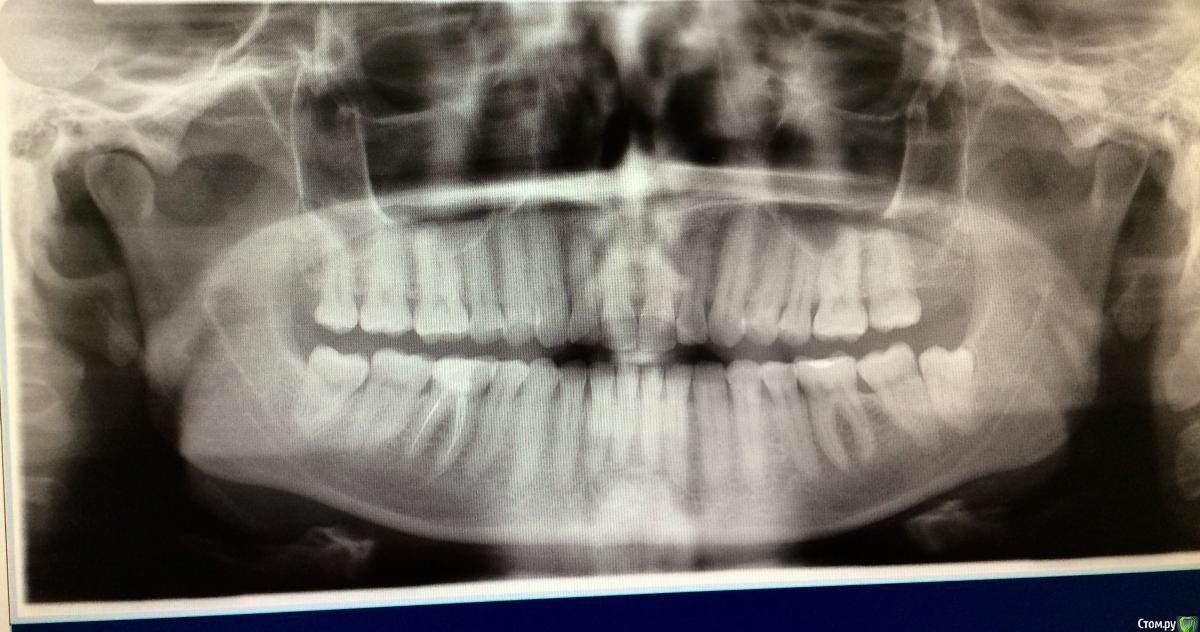

Larnary Опубликовано 28 июля, 2015 Автор Поделиться Опубликовано 28 июля, 2015 (изменено) Видно окклюзионнык интерференции в области 37 и 47.На днях удален 38 и дальше будут удалены остальные восьмерки. На ТРГ мне видится небольшая ретрузия верхних резцов,дистальный прикус. Так же левпя окклюзионная кривая более выраженная,чем правая Изменено 28 июля, 2015 пользователем Larnary 1 Ссылка на комментарий

Skip Опубликовано 29 июля, 2015 Поделиться Опубликовано 29 июля, 2015 На ТРГ мне видится небольшая ретрузия верхних резцов,дистальный прикус. Так же левпя окклюзионная кривая более выраженная,чем правая Доброе утро! Если отталкиваться от анализа ТРГ, то там нет выраженного дистального прикуса, хотя какие-то 0,2 мм. присутствуют, но это ерунда. Скелетное соотношение челюстей Класс I, но есть другая проблема, которая на скриншоте ниже обведена красным: http://i10.pixs.ru/storage/5/2/2/65456789jp_9935083_18202522.jpg Skeletal Deep bite или Скелетный глубокий прикус. Заметьте, не Зубной глубокий прикус, а именно Скелетный и это будет работать в Вашу пользу при планировании лечения. Если встречается комбинация глубокого Зубного и Скелетного, то эти случаи сложнее открыть. http://i11.pixs.ru/storage/5/3/1/0987645678_6395482_18202531.jpg В отношении верхних резцов, то всё правильно Вы отметили, они действительно в ретрузии (-4 мм.) и угол их инклинации уменьшен, как собственно и угол инклинации нижних резцов, а другими словами, мы имеем соотношение резцов 2-го подкласса. Это обстоятельство служит достаточно высоким риском развития внутрикапсулярных проблем ВНЧС. В вашем случае, интуиция мне как-то подсказывает, что там вероятно существует гипермобильность, но могу и ошибаться. Резцы 2-го подкласса могут объяснить и стриаемость этих зубов, учитывая, как Вы наверное знаете, дисгармонию между углом суставного пути и угла инклинации резцов Но вот ещё одно обстоятельство, на которое хотелось бы обратить внимание и которое нужно отметить в Вашем проблемном списке. Опять же, исходя из анализа ТРГ. Из этого анализа следует, что верхняя челюсть длинная и расположена в ретропозиции. Вы это никак уже не измените, но как при этом будет вести себя нижняя челюсть? Из собственной практики, я заметил, что нижняя челюсть, при этих обстоятельствах, частенько позиционируется кпереди в центральной окклюзии, обеспечивая, тем самым, нормализацию такой жизненно важной функции, как дыхание. И если Вы проведёте, к примеру, нейромышечную регистрацию физиологического положения нижней челюсти, а иными словами регистрацию прикуса, то вполне сможете обнаружить, что нижняя челюсть окажется в ретроположении. И получаем, в итоге, такой недоделанный природой Класс II, так ведь..? Это как раз то, когда повышая прикус, мы, впоследствии, сталкиваемся с проблемой т.н. двойного прикуса. Может нижняя челюсть и сметала всё мешающее ей на своём пути, когда постоянно стремилась находиться кпереди..? Кстати, при 2-ом классе нижняя челюсть практически всегда любит находится чуть кпереди, но это так, для кругозора... Есть ещё одно обстоятельство, которое может наносить сокрушительный удар по твёрдым структурам зубов. Оговорюсь сразу, что я не сторонник разных там теорий, так или иначе связанных с психикой, стрессом и так далее. В связи с этим у меня к Вам вопрос. Вы проводили монтаж моделей в артикуляторе с лицевой дугой или по средним значениям? Если с лицевой дугой, то хотелось бы взглянуть, как там модель верхней челюсти расположена в пространстве артикулятора. Нет ли там бокового смещения модели от центра верхней рамы..? То, что с левой стороны окклюзионная кривая глубже, то это носит адаптационной характер, связанный с левым суставом, поэтому нужно провести мониторинг ВНЧС, на предмет внутрикапсулярных расстройств этого сочленения (объём вертикальных и горизонтальных движений ROM). На ТРГ, кстати, можно заметить, как раздваивается нижний край тела нижней челюсти и это неспроста. 3 Ссылка на комментарий

Skip Опубликовано 3 августа, 2015 Поделиться Опубликовано 3 августа, 2015 Со слов Коиса понял, что в данном случае было бы достаточно создать достаточное функциональное пространство для резцов нижней челюсти, путем брекетов например, вывести передние резцы в/ч в протрузию Не самое лучшее решение при глубоком прикусе. Довольно часто приходится видеть, как попытки решения проблем глубокого прикуса терпят неудачу из-за непонимания принципов передней направляющей. Первое, с чем Вы здесь сразу можете столкнуться, когда будете "выводить резцы в/ч в протрузию", показано на рисунке ниже: http://i11.pixs.ru/storage/4/5/6/09765ukeng_6235790_18261456.jpg Верхние резцы будут наталкиваться на нижнюю губу, из-за чего могут возникнуть проблемы с фонетикой, да и эстетически ничего хорошего. Мало того, полученный результат будет крайне нестабилен вследствие нарушенного нейромышечного равновесия нейтральной зоны, об этом можно почитать у Доусона. Поэтому грамотные ортодонты, зная об этом, проводят не вестибулярный наклон, а интрузию верхних и нижних резцов. Да и говоря в общем, проблема стираемости, при глубоком прикусе, обусловлена не "малым оверджетом", как выразился Александр. Основная проблема состоит в том, что при отсутствии устойчивых удерживающих контактов нижних резцов с верхними в ЦС, происходит их зубоальвеолярная экструзия. Глубокие прикусы, если там решена проблема этих удерживающих контактов на нёбной поверхности коронок верхних резцов , будет среди самых устойчивых видов окклюзии, т.к. с disclusion в боковых отделах здесь почти не бывает проблем. С интерференциями в задних отделах нужно тоже разобраться и делать это нужно в ЦС, перенеся модели в артикулятор с лицевой дугой. На видео можно проследить, к эти интерференции могут стать причиной стираемости передних резцов. http://www.youtube.com/watch?v=2wRffJl82dc http://www.youtube.com/watch?v=My3K-B78iLg 1 Ссылка на комментарий

Maverick Опубликовано 9 августа, 2015 Поделиться Опубликовано 9 августа, 2015 (изменено) Думаю в данном кейсе интрузия резцов будет нежелательна, десневые контуры фронтальной группы зубов выглядят хорошо, ровно, нет разницы в высоте(если конечно не были внесены изменения в контур десны, типа пластик) . И тут не дентальный глубокий прикус, а скелетный, как было отмечено выше. Еще один негативный момент в интрузии, который играет важную роль , так это искусственное состаривание пациента, верхняя губа имеет свойство опускаться со временем, что только ухудшит картину эстетики улыбки. Экспозиция резцов очень важный критерий в планировании лечения, тут надо отталкиваться от возраста пациента. Думаю у данного пациента, учитывая возраст, позицию фронтальных зубов , уровень десны идеально будет завысить прикус в боковом отделе и вывести в небольшой вестибулярный наклон фронт на брекетах, либо как упоминалось выше за счет изменение наклона коронковой части, путем керамических реставраций, что удобнее для пациента в плане финансовых и временных затрат. P.S. Такое ощущение , что есть определенные проблемы с клыковым ведением, поэтому и интерфреннции возникают в боковом отделе. Поэтому хорошо было бы увидеть все в артикуляторе, чтобы уже точно знать причину Угол межрезцовый идеальный 132 градуса плюс минус 10 град. Изменено 9 августа, 2015 пользователем Maverick 2 Ссылка на комментарий